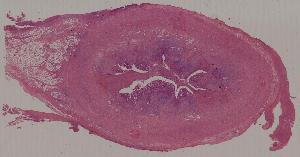

19.Phlegmonous appendicitis